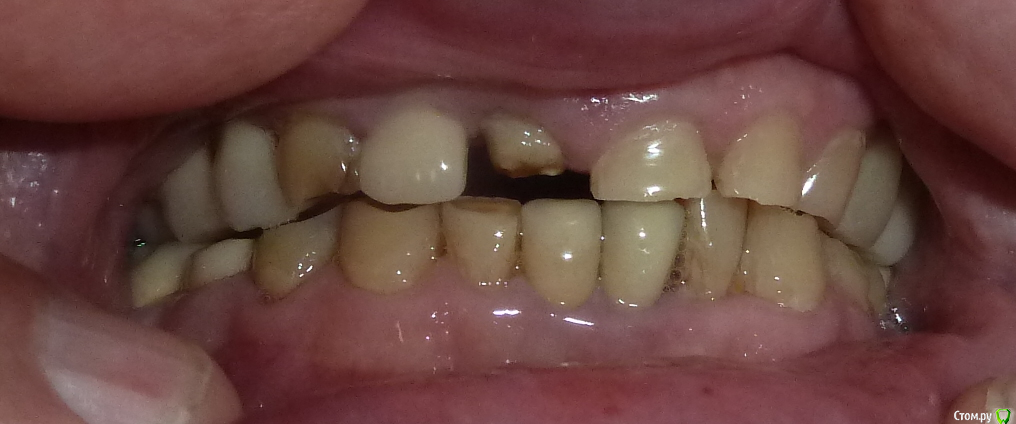

adent Опубликовано 22 июня, 2020 Автор Поделиться Опубликовано 22 июня, 2020 покажите фото зуба во рту, и фото с сомкнутыми зубами Мой возраст 79 лет. Фото прикреплены к сообщению.Спасибо! Ссылка на комментарий

adent Опубликовано 20 июня, 2020 Поделиться Опубликовано 20 июня, 2020 Здравствуйте! Спала коронка с зуба номер 8.Он обточен и остаток зуба имеет размер примерно 2 мм на 2 мм.Посоветуйте пожалуйста.Может можно (целесообразжно) поставить штифт в остаток зуба чтобыновая коронка держалась надежнее? Спасибо! АнатолийP.S. Снимок прикреплен Ссылка на комментарий

adent Опубликовано 20 июня, 2020 Автор Поделиться Опубликовано 20 июня, 2020 Снимок переднего зуба номер 8 прикреплен здесь.Прошу прощения по неопытности не получилось прикрепить файл в первом сообщении. Ссылка на комментарий